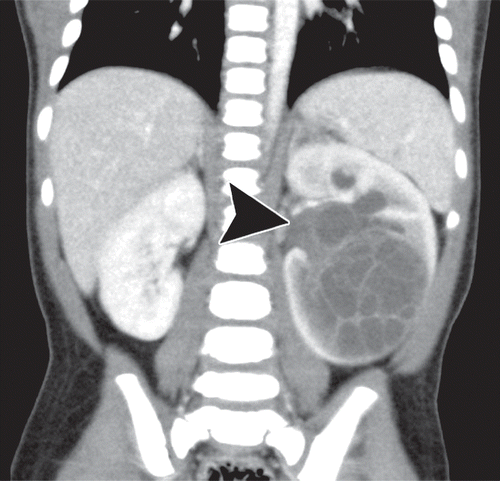

Nephroblastomatosis

Picture of nephroblstomatosis + Wilms

Screening ultrasound every 3 months until patient turn 8